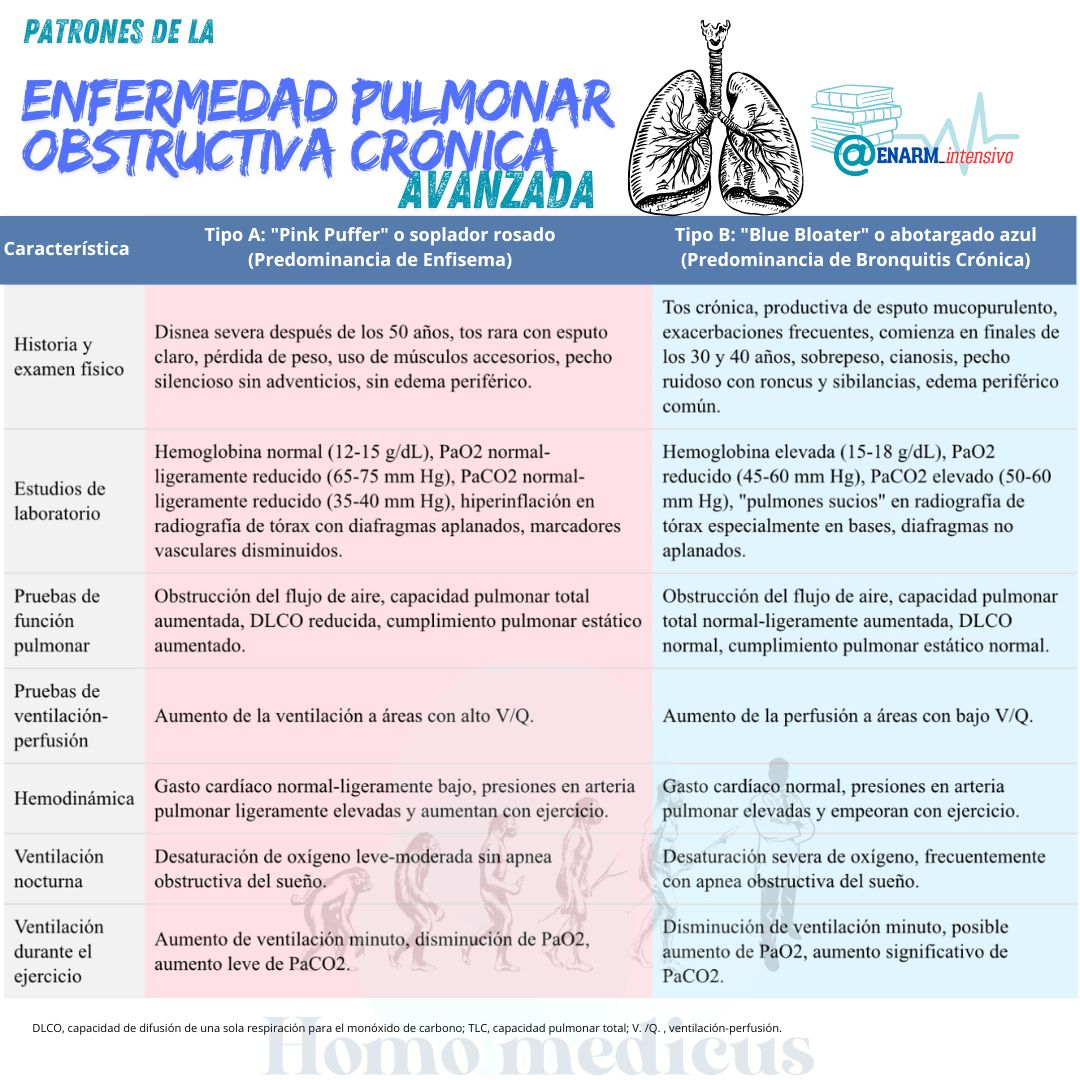

Conforme avanza el curso de la EPOC, suelen distinguirse dos patrones de síntomas clínicos: el «disneico acianótico» y el «congestivo cianótico». La mayoría de los pacientes presentan características de ambos trastornos. En el disneico acianótico, la disnea es prominente y se acompaña de una coloración normal de la piel debido a la falta de oxígeno (cianosis). En contraste, en el congestivo cianótico, además de la disnea, los pacientes pueden mostrar una coloración azulada de la piel debido a la hipoxemia severa.

Al inicio del curso de la EPOC, las pruebas de función pulmonar (PFT) pueden revelar anormalidades específicas que indican obstrucción del flujo de aire. Entre estas, se observa un volumen de cierre anormal y una reducción en los caudales de la mitad de la expiración, marcando la presencia de obstrucción bronquial. La disminución del Volumen Forzado Espiratorio en el primer segundo (FEV1) y la relación FEV1/Capacidad Vital Forzada (FVC) (%FEV1 o FEV1/FVC) confirman esta obstrucción y son indicativos de la gravedad de la enfermedad. En etapas avanzadas, la capacidad vital (FVC) también se ve significativamente reducida, reflejando una disminución global en la función pulmonar.

Además de la espirometría estándar, las mediciones de los volúmenes pulmonares proporcionan información adicional crucial. Se observa un aumento en el volumen residual (RV) y en la capacidad pulmonar total (TLC), junto con una relación RV/TLC elevada, lo cual es indicativo de atrapamiento de aire e hiperinflación pulmonar. Estos hallazgos son particularmente comunes en pacientes con enfisema, una de las formas clínicas de la EPOC.

En el contexto de la obstrucción del flujo de aire, la capacidad de difusión del monóxido de carbono de una sola respiración (Dlco) es una medida sensible para evaluar el intercambio gaseoso en los pulmones. Una reducción severa en la Dlco sugiere cambios anatómicos asociados con el enfisema y se asocia con desaturación de la oxihemoglobina durante el ejercicio físico, así como con la presencia de hipertensión pulmonar coexistente.

La medición de gases en sangre arterial (ABG) desempeña un papel específico en la evaluación y manejo de los pacientes, aunque no se considera necesaria de forma rutinaria al inicio de la enfermedad, a menos que ciertos criterios clínicos estén presentes.

Inicialmente, al inicio de la EPOC, las ABG típicamente no muestran anomalías significativas, excepto por un aumento en el gradiente alveolo-arterial de oxígeno (A-a-Do2), que indica una alteración en el intercambio gaseoso pulmonar. La necesidad de medir ABG se reserva principalmente para situaciones donde se sospeche hipoxemia o hipercapnia, o cuando pruebas de función pulmonar como el FEV1 o la capacidad de difusión del monóxido de carbono (Dlco) son significativamente reducidas, menos del 40% de lo esperado.

La hipoxemia es una característica temprana en la enfermedad donde predomina la bronquitis crónica, mientras que la hipercapnia y la acidosis respiratoria compensada se desarrollan a medida que la enfermedad progresa. Estas condiciones pueden empeorar durante el sueño, el ejercicio físico y durante las exacerbaciones agudas de la enfermedad, donde los pacientes experimentan un aumento en la obstrucción de las vías respiratorias y una mayor dificultad para mantener el equilibrio ácido-base.